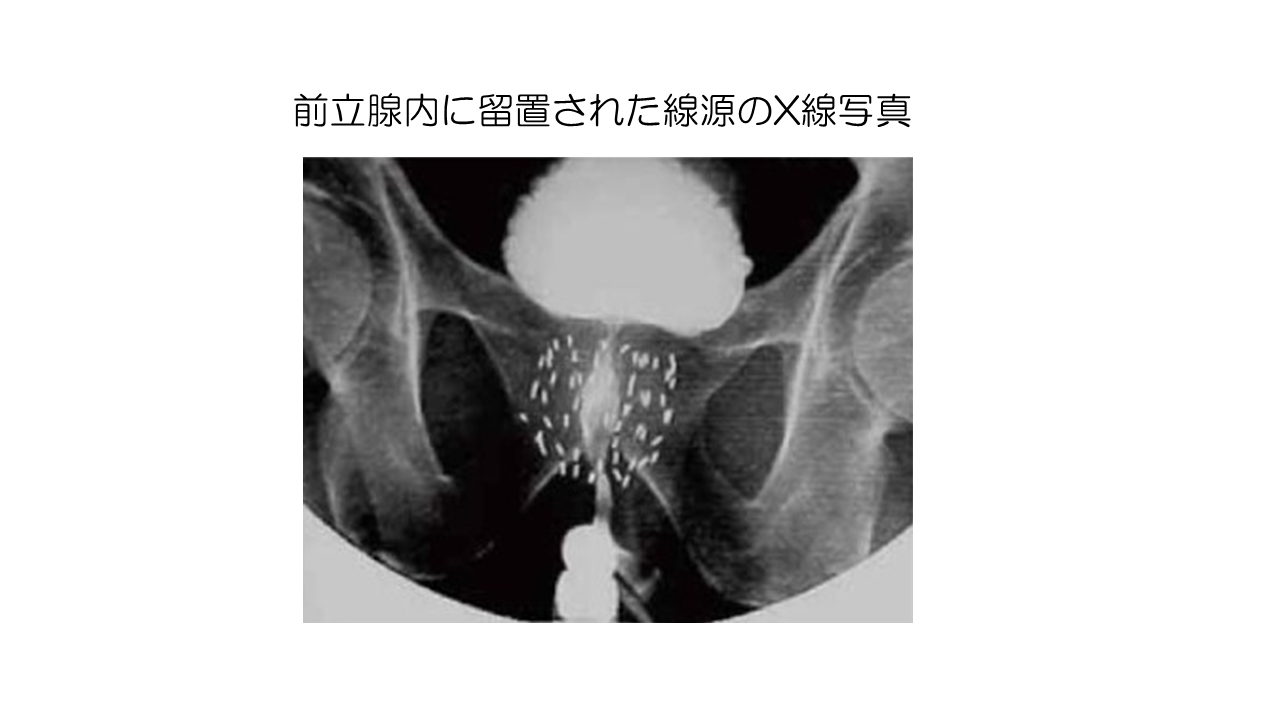

治療中、医師または技師は装置を使用して放射線を集中させ、がんの部位に照射します。人は自宅ではなく、病院または治療センターで治療を受けます。従来の放射線とは異なり、陽子線治療はほぼすべての放射線をがん部位に照射し、近くの組織を保護します。